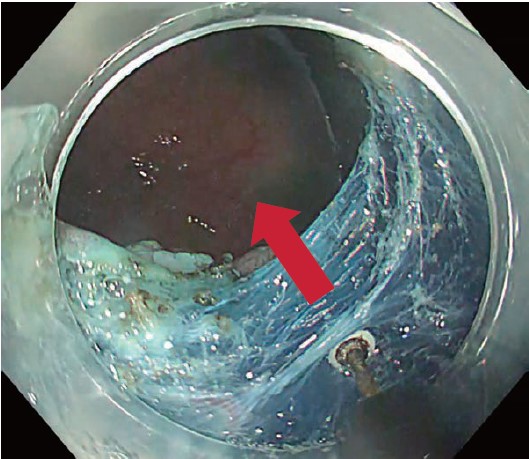

However, this added safety can decouple knife motion from dissection speed, tending to shallow the dissection layer (Fig. 3). Traction solves this completely. Clip-with-line traction stands the submucosa upright – like the adductor muscle of a scallop – enabling efficient, rapid dissection with the 3.5-mm blade while preserving the safety benefits of the ITknife nano tip and the safety of the “not excessively sharp” blade (Fig. 4).

If patient movement or hiccups slow the procedure, I immediately use the ITknife nano with thread traction; the case can still be finished quickly while exploiting the knife’s safety.

Once the flap was raised, clip-with-line traction was applied, and submucosal dissection was completed fairly quickly with the ITknife nano (Fig. 7, Movie 1). With traction in place, the theoretical risk of perforation approaches zero. Dissection is performed in coagulation mode, melting the tissue while keeping the white insulated back of the tip visible through the blue submucosa (Fig. 8).